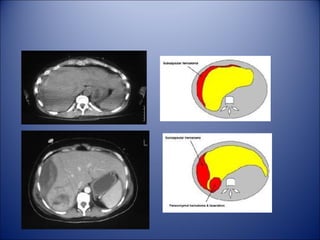

• CT Scan

– The standard evaluation method for stable pt

– Performed with water soluble oral and

intravenous contrast

• CT Scan – The standard evaluation method for stable pt – Performed with water soluble oral and intravenous contrast